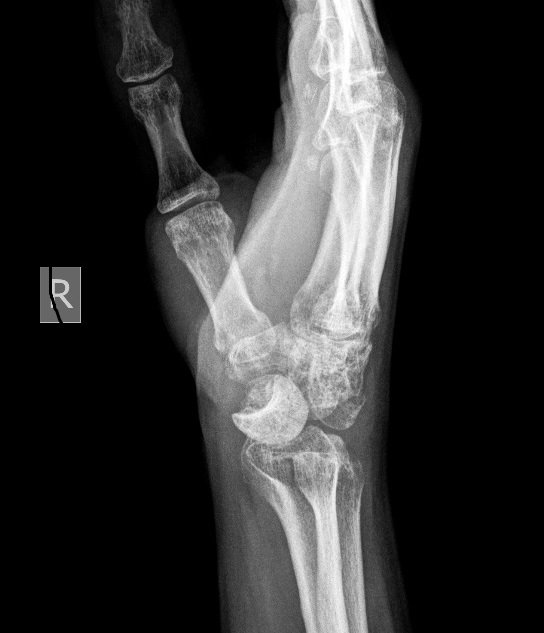

• Мнения: 3

Здравейте! Преди 4 месеца си счупих китката. Два месеца ходя на раздвижване, но болката остава. Направих нова снимка и се оказва, че имам и изкълчване. Посъветвах се с няколко специалиста и всички са на различно мнение. Един казва, че трябва да се оперира, друг, че е късно за операция вече, трети, че с още раздвижване, масаж и рехабилитация болката ще изчезне... Не знам какво да правя, моля за съвет. Ето и рентгеновата снимка, на която се вижда изкълчването